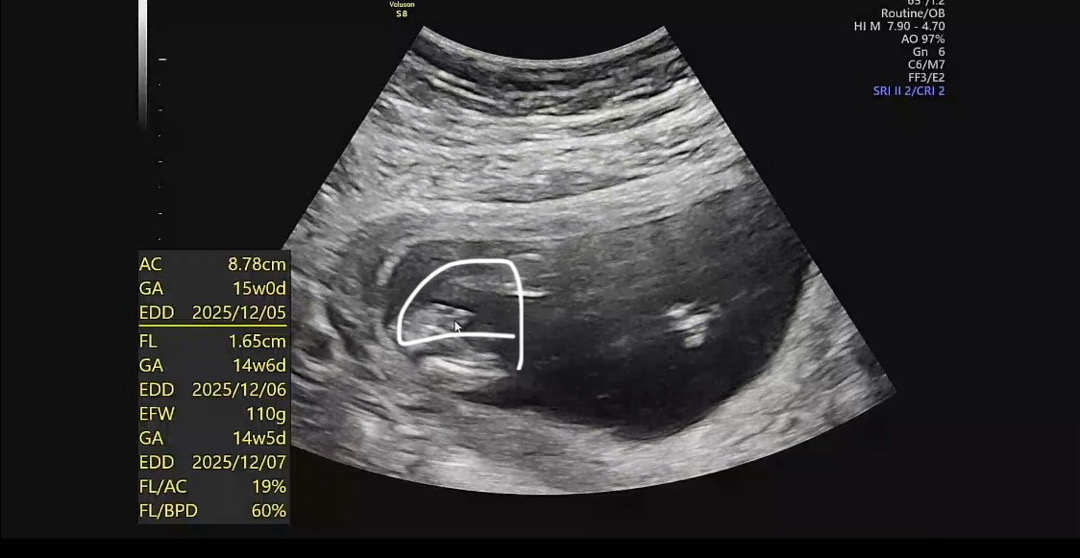

15주 각도법,,,

각도법 보고싶은데 애기가 옆으로 안누워잇고 자꾸 정면을 보여주는데 그럼 각도법 못보겟죠.,? 그리고 제가 사진봤을땐 저게 고추같은데 선생님은 아직 모르겟다하시던데 어떤거같으세요,,? ㅠ